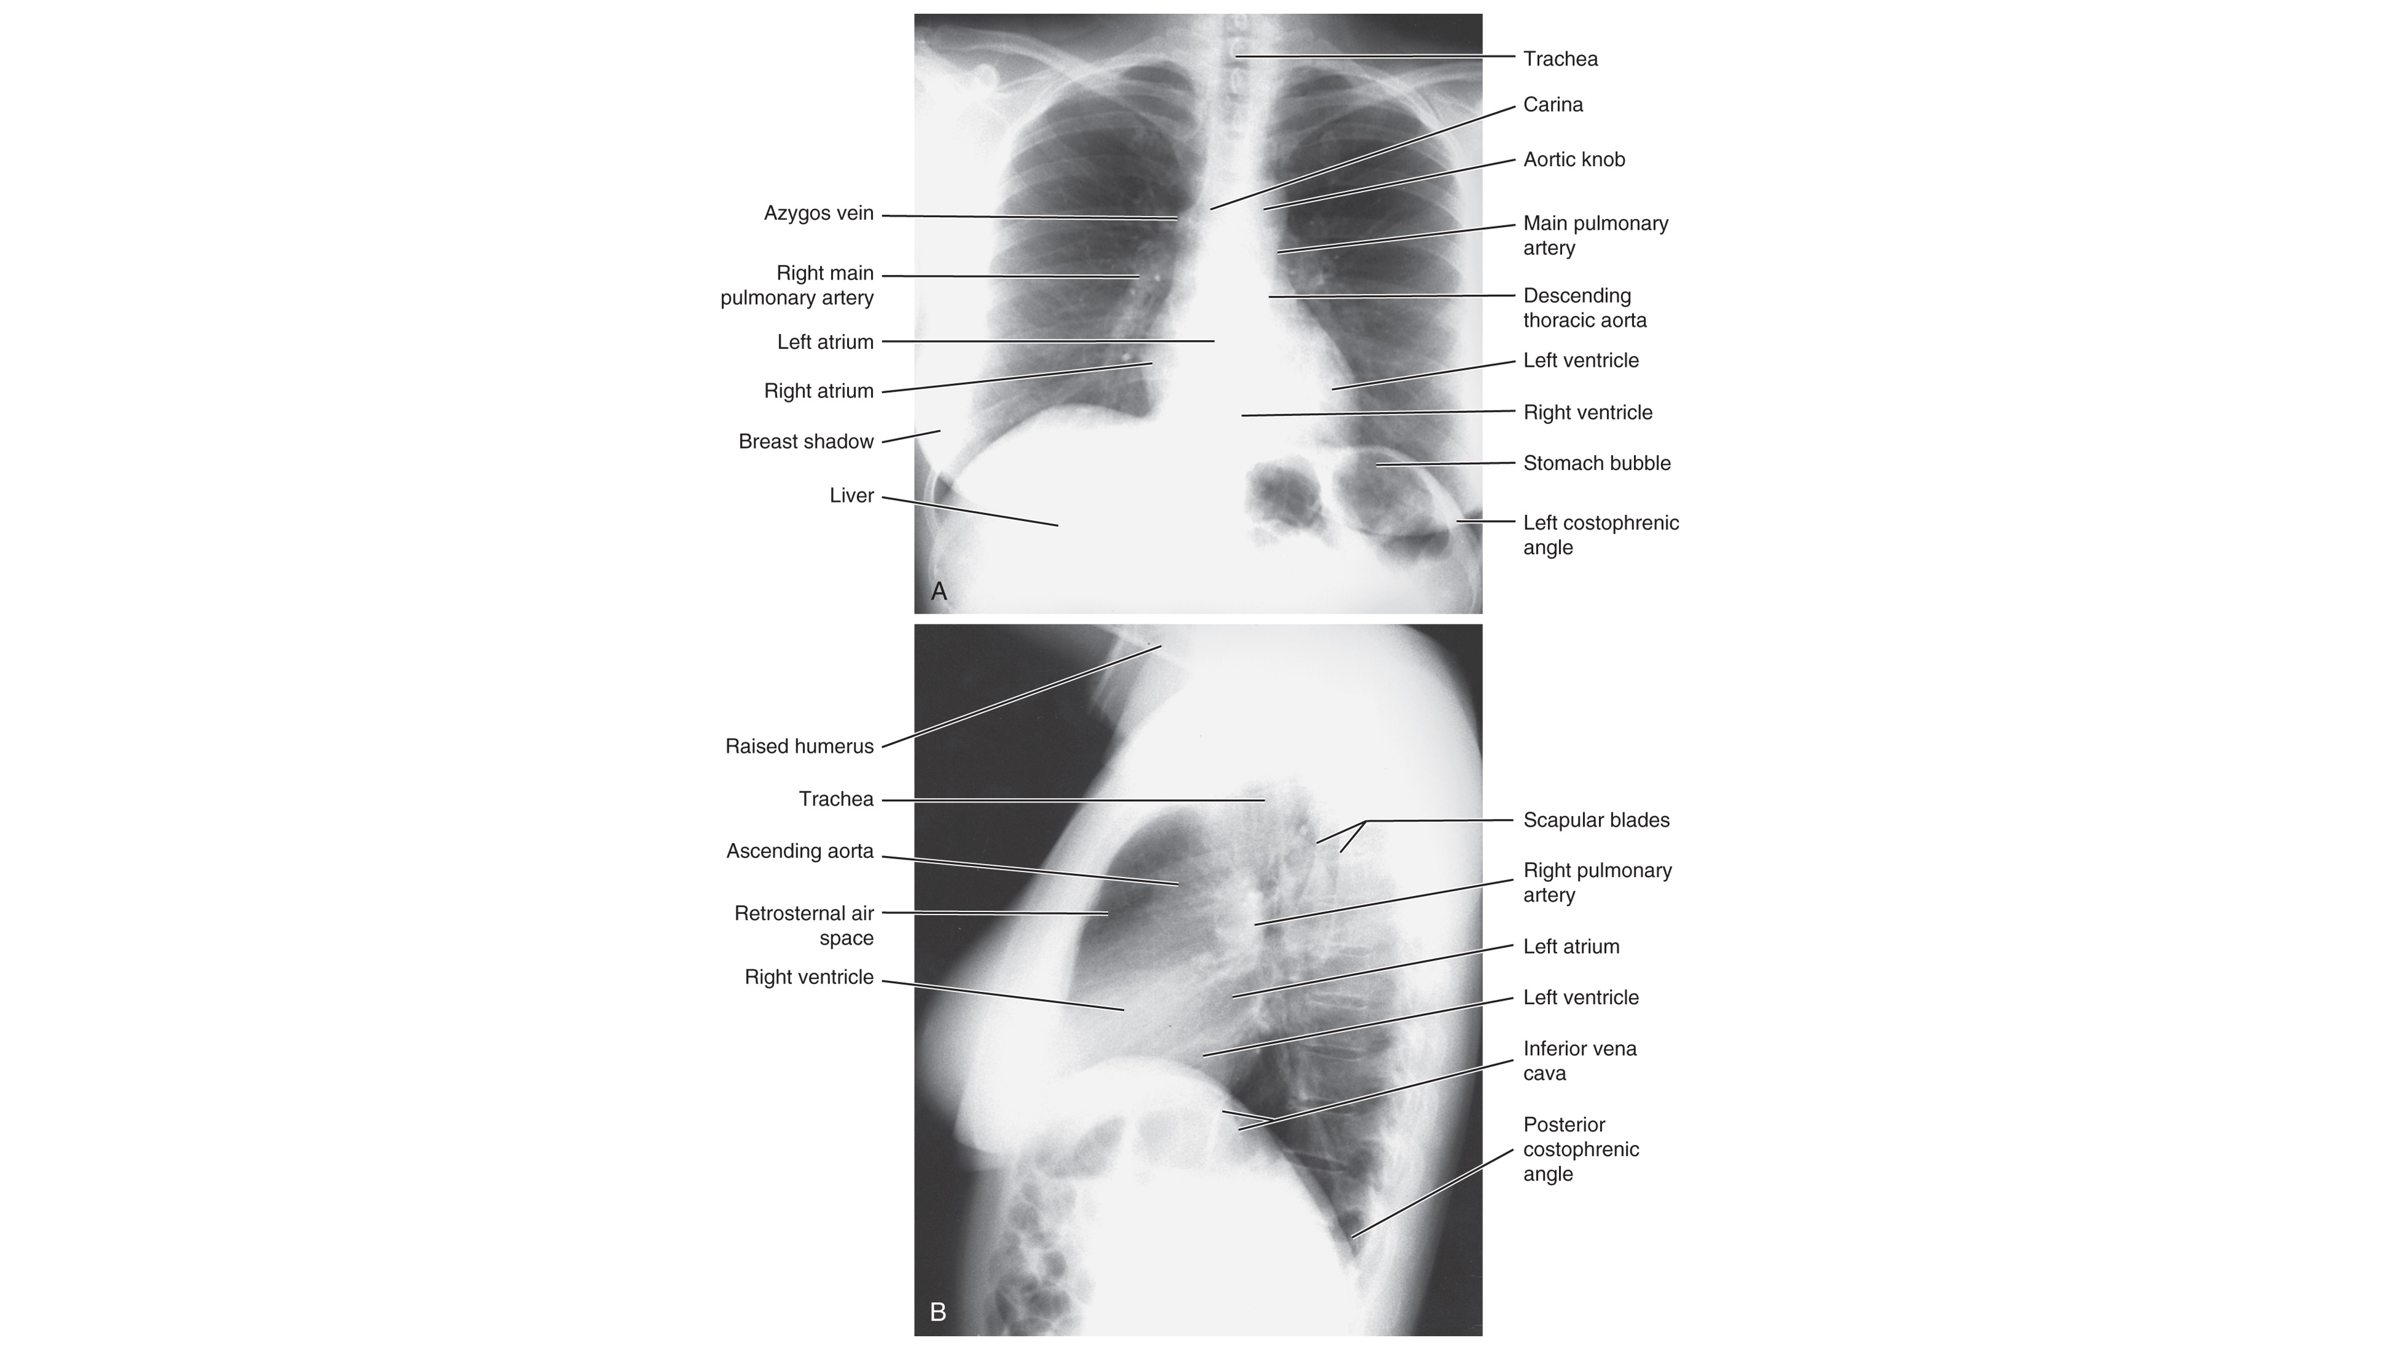

Normal CXR (PA & Lateral)

Name the mediastinal contours according to the numbers

1- superior vena cava

2- right atrium

3- inferior vena cava

4- aortic arch or knob

5- left pulmonary trunk

6- left pulmonary artery

7- left atrium

8- left ventricle

9- left cardiophrenic angle

Name the structures according to letter

A – Trachea

B – Clavicle

C – Right Atrium

D – Diaphragm

E – Cardiophrenic angle (Costocardio)

F – Left upper lobe

G – Gastric Bubble

H – Left Hilum